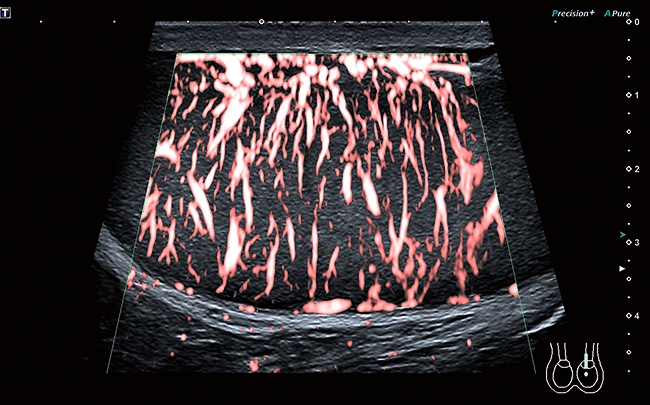

• Технология SMI для визуализации микроциркуляторного русла и отображения низкоскоростного кровотока в микрососудах

Цветной доплер

Эта функция поможет в исследованиях сердечно-сосудистой системы. Вы сможете выделить цветом характер кровотока на интересующем вас участке. Кровяной поток, идущий от датчика, отображается синим, к датчику – красным. Турбулентный поток фиксируется в сине-зелено-желтой цветовой гамме.